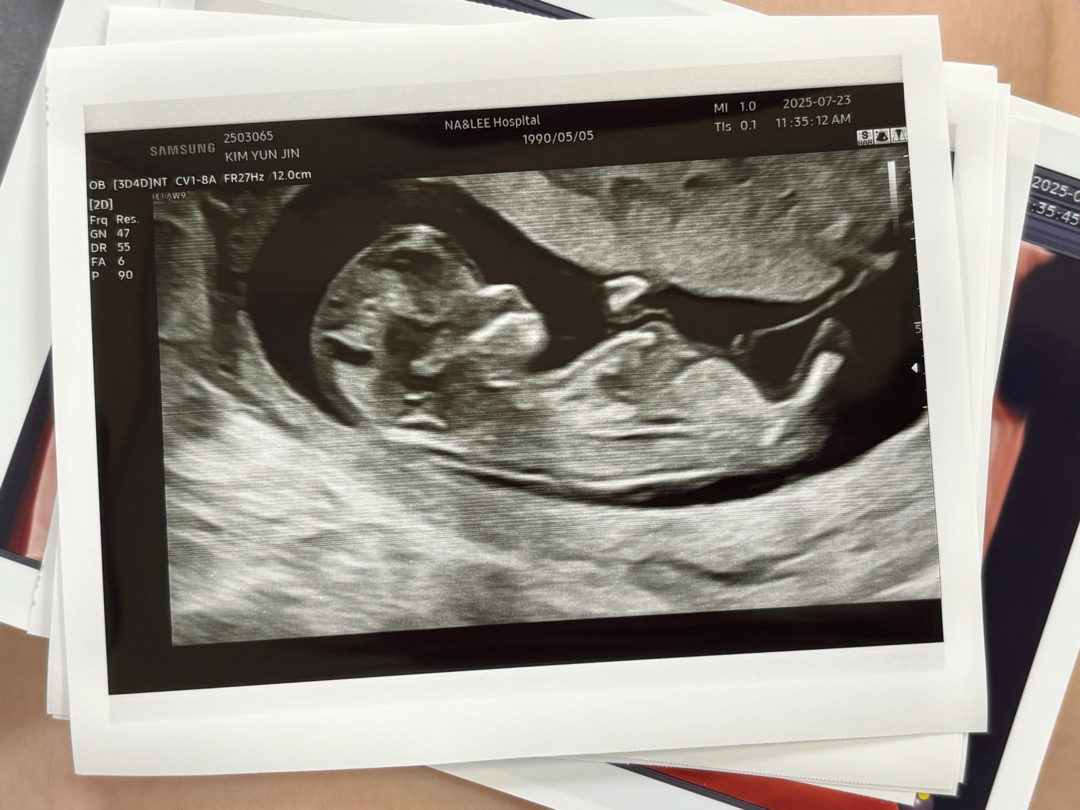

12주차 각도법!!!!

성별이 어떻게 될까요~? 딸? 아들?

각도가 보이는 사진없어요?

생식기쪽이 제대로 안보이네요ㅠ 그래도 굳이 말하자면 딸에 가까운거같아요!